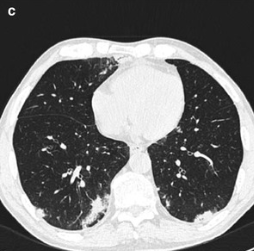

Pneumonia

Among febrile neutropenic patients with a “normal” chest x-ray,

up to 60% of patients may have findings of pneumonia on CT

Common CT findings

Bronchoscopy